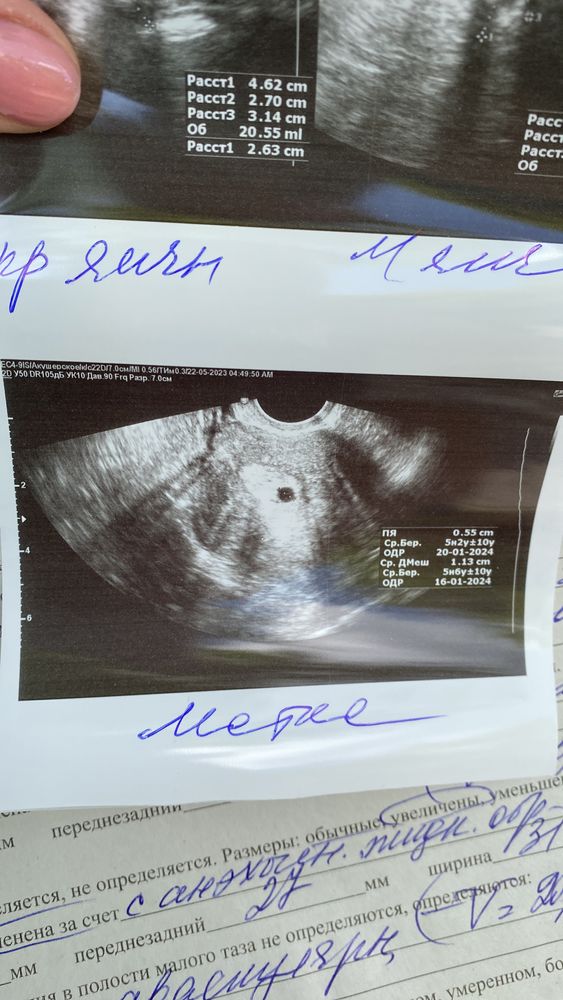

Начнем с того, что мой цикл очень при очень не регулярный. Кроме того, что месячные идут как хотят, больше ни чего не беспокоит. Хотя раньше все было Гуд с ними. Так вот решили мы с мужем, что хотим еще малыша. И так скажем перестали предохраняться. Мес были 25.03.2023, начали стараться над процессом с 13.04. По сей день месячных так и не было. Сделала кучу тестов. Я наверно обогатила все аптеки на районе, заветных полосок так и не увидела. Ходила сегодня к гинекологу и на узи. Увидела образование в матке. Но врач сама не понимает, беременность это или образование какое то. Сказали прийти через 2-3 недели на прием. Я изведусь вся. Прикрепляю фото узи и протокол.ставят срок если это беременность, 5.2 недели. Так то все подходит. Но вот почему тесты до сих пор тогда молчат.